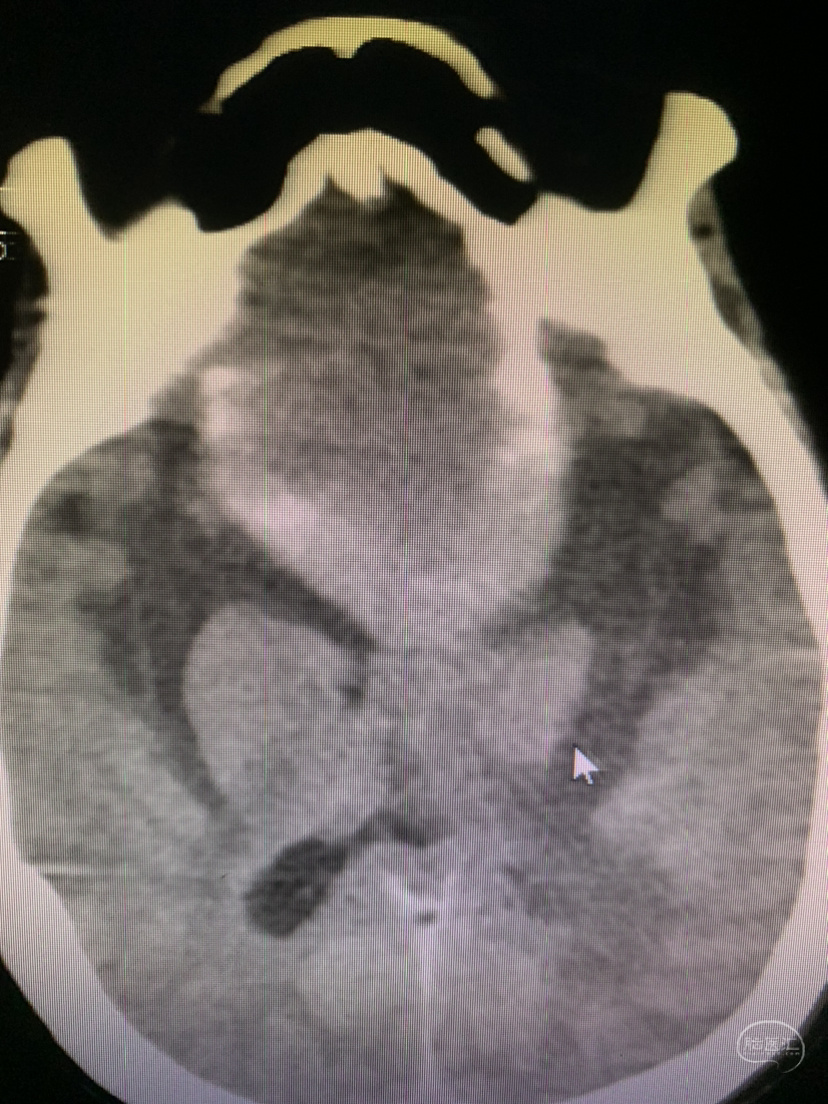

术前CT

神志昏迷双瞳散大对光反射迟钝入院,入院后甘露醇脱水加地米静滴后患者神经功能有改善,能摸索定位,瞳孔反射改善。考虑占位大直接切除可能出血多,拟术前栓塞处理,但造影发现栓塞不易风险高后放弃栓塞。

术前CT